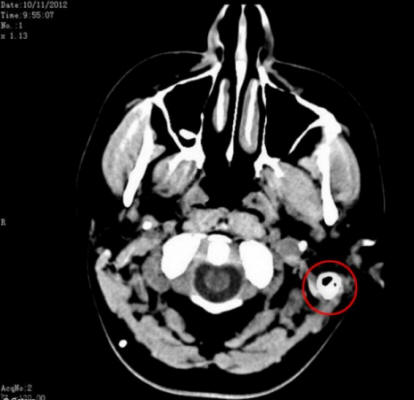

Sam kutsuttiin joukkoon ammattilaisia, jotka he epäilivät, että hänellä voi olla aivokasvain. Onneksi jälkeen suorittamalla sarjan testit, aivokasvain suljettiin pois luettelo taudin mahdollisista syistä. Lääkärit eivät kuitenkaan pystyneet selvittää, mitä hänelle tapahtui. Asiantuntijat selvittivät totuuden syy hänen terveysongelmiinsa vasta lannerangan jälkeen punktio.

Ihmisen aivoja ympäröi neste, joka suojaa aivoja alkaen osumasta kallon seinään, mutta Samin vartalo osoittautui olevan tuottaa tämän nesteen kolminkertaisesti normiin. Jopa sen jälkeen diagnosoimalla ja ottaen 17 erilaista lääkettä päivässä, Sam kärsi edelleen kauheista päänsärkyistä.